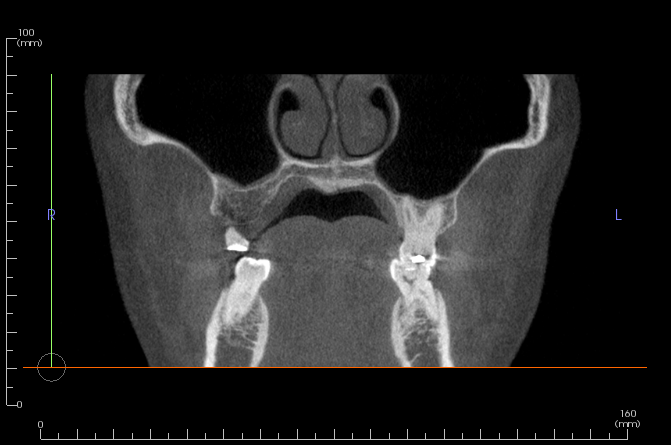

Sinus CT scan

The system uses a deep learning model based on Ultralytics YOLO to analyze dental CT images.

It detects key anatomical structures and estimates sinus-related angles to help assess potential surgical risks.

Our system supports standard dental CT or CBCT images.

For the best results, images should clearly show the maxillary sinus region and surrounding teeth structures.